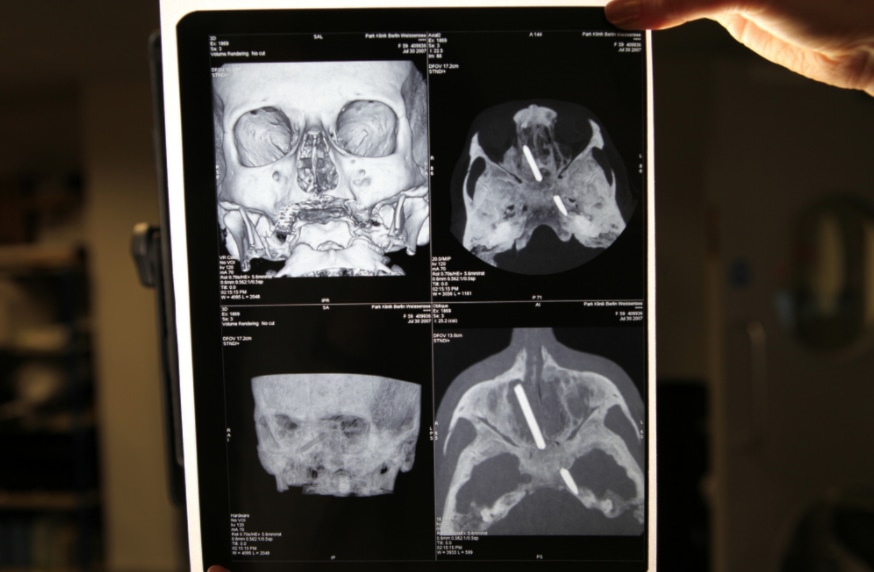

Хирург из Италии Серджио Канаверо заявил о первой в истории успешной пересадке головы человека. Операция была проведена на трупе в Китае и продолжалась в течение 18 часов. Врачам удалось восстановить нервы, кровеносные сосуды и позвоночник, сообщает The Telegraph.

Канаверо заявил, что в операции по пересадке головы поучаствовали китайский хирург Жень Сяопин и специалисты Медицинского университета Харбина, которые в 2015 году успешно трансплантировал голову обезьяне.